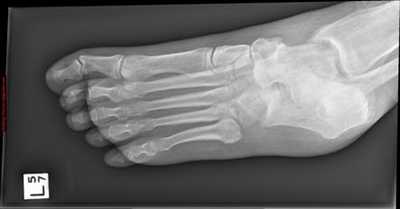

Рентгенологическое исследование

Для диагностики повреждения сустава Шопара делают рентген, КТ и МРТ. На передне-задней рентгенограмме определяют величину пяточно-кубовидного угла. Проводят одну касательную к наружному краю кубовидной кости и вторую касательную к наружному краю пяточной кости. В норме угол между касательными колеблется в пределах от 0 до 5°. Увеличение угла свидетельствует о нарушении стабильности пяточно-кубовидного сочленения. КТ во фронтальной и сагиттальной плоскостях позволяет выявить дефект суставных фасеток, смещение костей при вывихе и фрагментацию костей при переломе. КТ, по сравнению с рентгенографией, является более информативным методом диагностики. МРТ позволяет выявить дефекты отдельных связок.

Рис. 9. Переломо-вывих в суставе Шопара

Консервативное и оперативное лечение